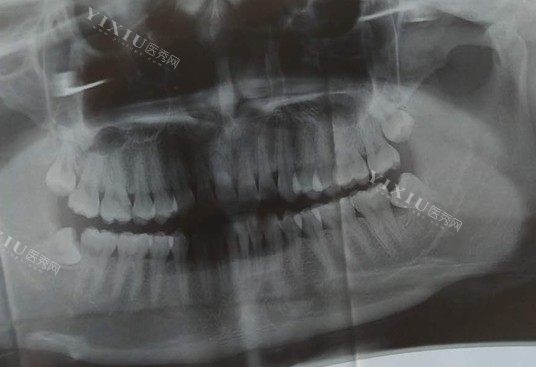

牙齿拍片是口腔医生在诊断病情时的重要辅助手段。通过牙齿拍片,医生可以清晰地观察牙齿及周围组织的情况,从而帮助确诊各种牙齿问题,如龋齿、牙周炎、牙髓炎等。此外,牙片还可以发现一些隐匿的疾病,如牙齿根尖周围的感染、牙齿裂口等。因此,拍牙片是确诊牙齿问题、制定有效治疗方案的重要步骤。

通过牙齿拍片,医生可以发现许多患者未察觉到的牙齿问题,包括但不限于以下几种:

龋齿:牙片可以清晰展示牙齿表面的蛀洞和损坏情况,帮助医生进行相应的修复和治疗。

牙周炎:牙片可以显示牙龈下的骨质破坏情况,有助于及早发现和治疗牙周炎。

牙髓感染:牙片可以显示牙髓腔是否感染,有助于确定是否需要进行根管治疗。

牙齿位置异常:牙片可以检查牙齿的位置是否正常,是否存在拥挤、错位等问题,为矫正牙齿提供参考依据。